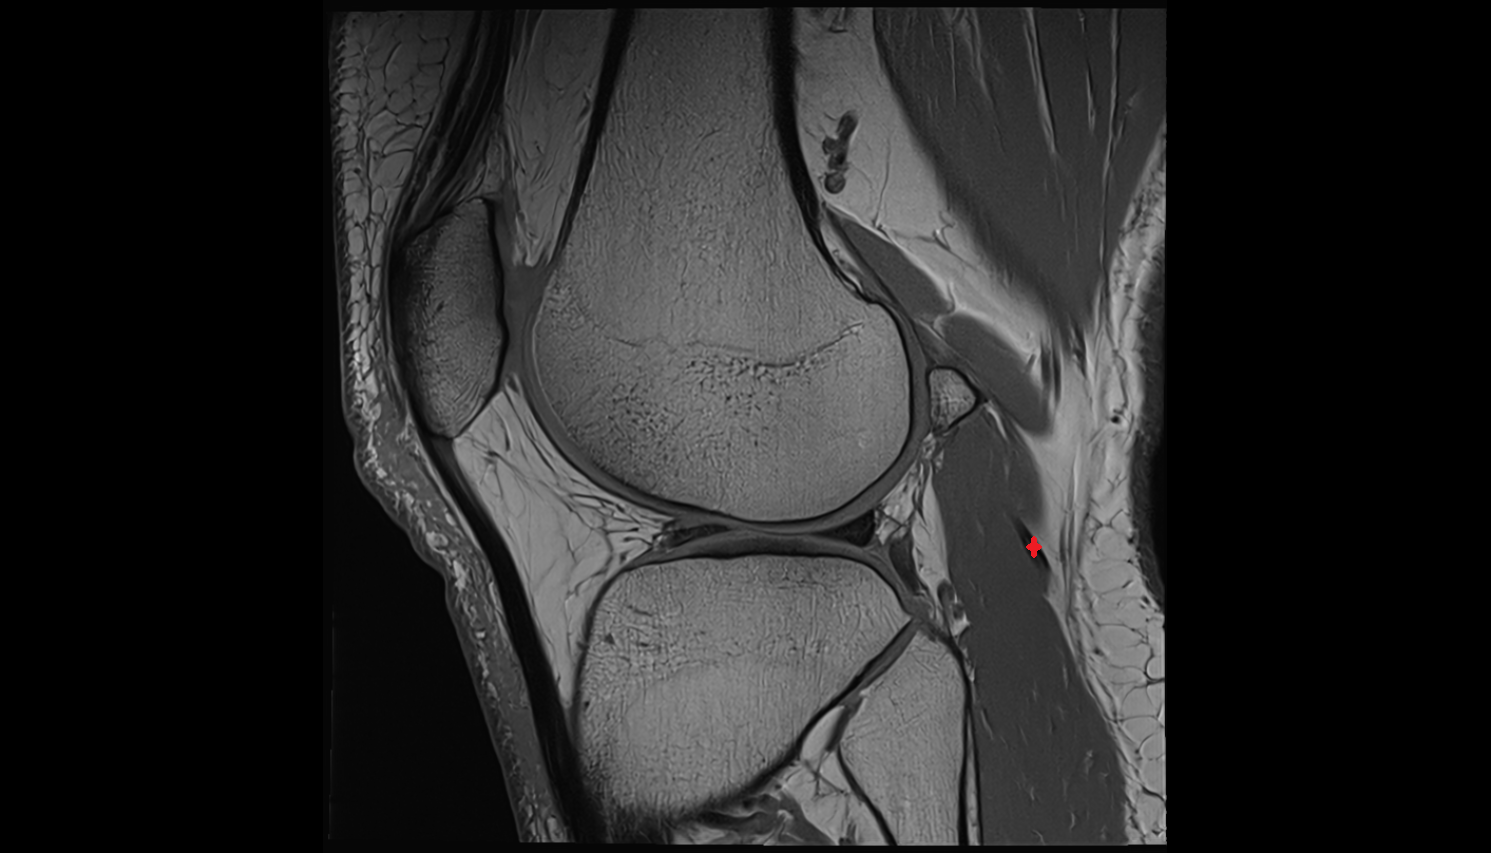

- Medial collateral ligament

- Lateral collateral ligament

- Anterolateral ligament of knee

- Oblique popliteal ligament

- Arcuate popliteal ligament

- Knee Joint